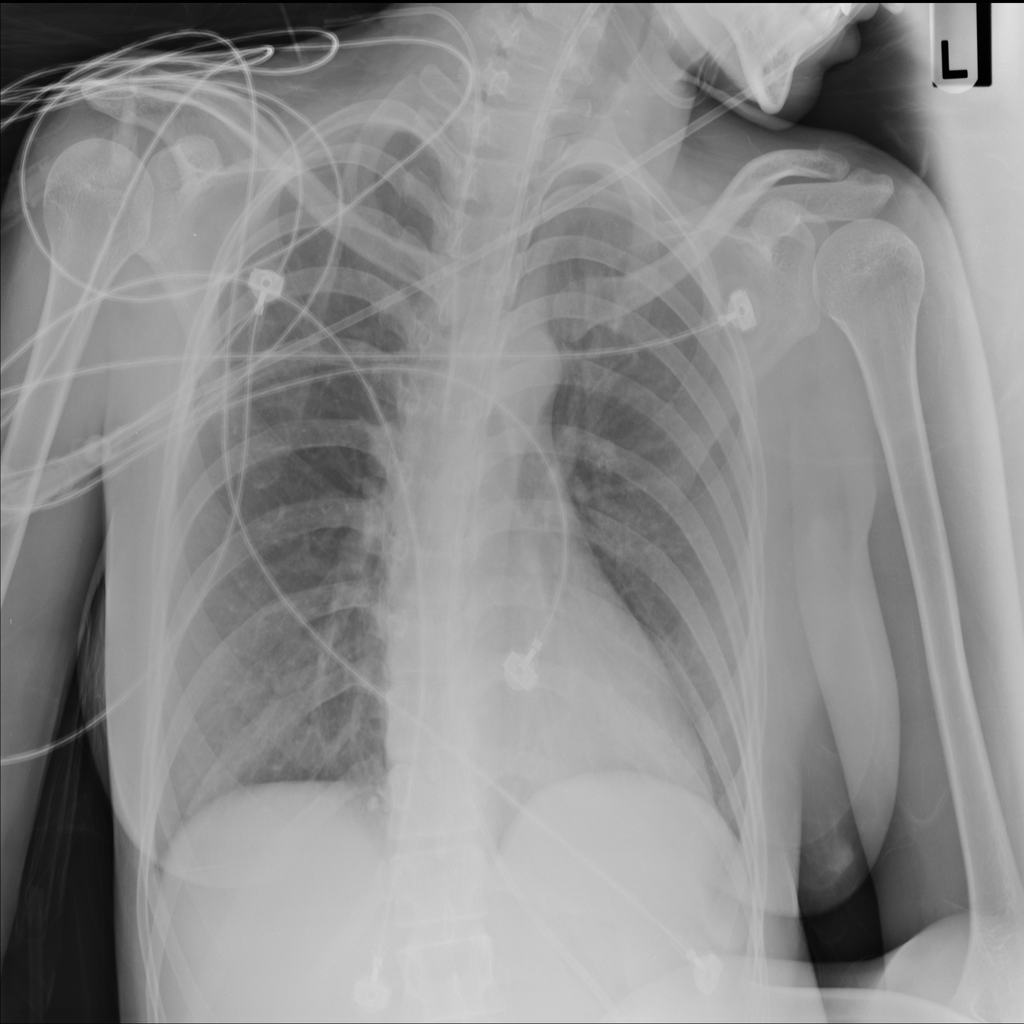

PAT-4C32 · IMG-001Pneumonia

PAT-4C32 · IMG-001

AP